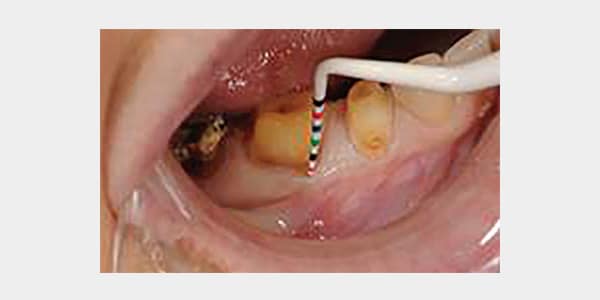

5 mm of recession is easily assessed as a result of the excellent contrast between the Colorvue probe and exposed root surface. In addition, the Colorvue probe enhances measurement of periodontal attachment loss.